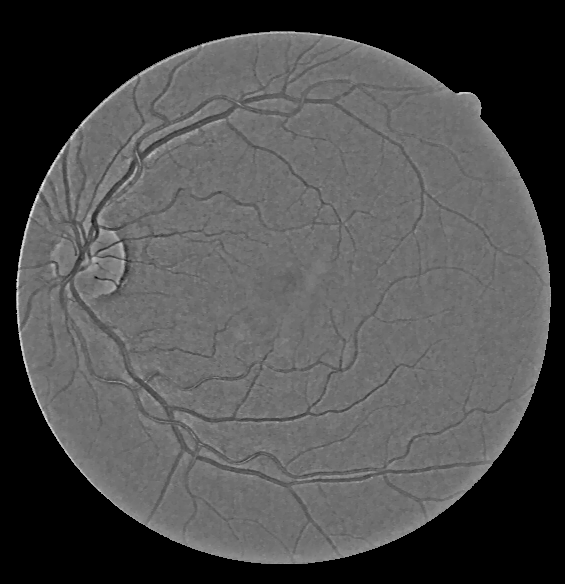

Detail Layer Enhancement

Red and Green detail layers are passed through a Gaussian filter, keeping in mind that a Gaussian filter is essentially a low pass filter and it will somewhat blur the edges of the veins, making them thicker and more prominent, while removing other noise and artefacts. The execution of the next step differs a bit from the original reference paper. Blue layer does not carry much information and hence is not used.

First Row: RGB detail layers

Second Row: Old detail layer, New enhanced detail layer

The enhanced detail layers are merged with the corresponding base layers to form the final output according to the equation: \begin{equation} I_{out}^c = I_{correct-base}^c + \alpha^c I_{enhance-details}^c \end{equation}

Corrected base merged with enhanced detail layer to give output

The output is clearly much better than CLAHE visually.